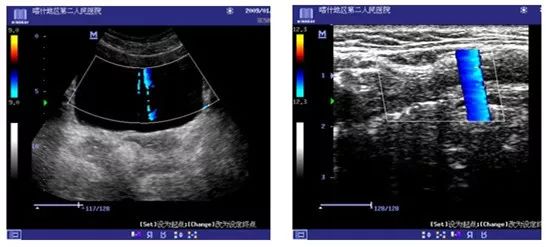

1、超声设备电源线与插座接触不良引起的干扰(DC-6)

现象:干扰束会随机出现在图像的不同区域

原因:电源线与电源插座接触不良,电极易产生电离火花引入电磁干扰,造成图像干扰现象。

处理措施:更换插座孔或新插排。